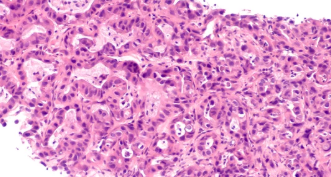

췌장은 위 뒤쪽에 위치한 기관으로, 소화 효소 분비와 인슐린·글루카곤 등 혈당 조절 호르몬을 생산하는 장기입니다.

췌장암은 이 췌장 조직에 비정상적인 암세포가 생겨 빠르게 퍼지는 악성 종양으로, 특히 **췌장 머리 부분(두부)**에 가장 자주 발생합니다.